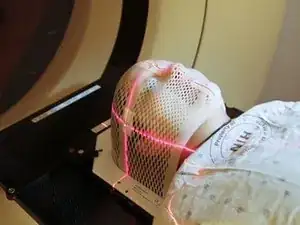

Medical imaging is the process of creating visual representations of the internal structures of the body beneath the skin and bones. These images can then be used for clinical analysis, diagnosis and discovery of abnormalities, and to create plans for medical intervention. Medical imaging uses a variety of technologies based on the area of analysis, including but not limited to “X-ray radiography, magnetic resonance imaging, ultrasound, endoscopy, elastography, tactile imaging, thermography, medical photography, and nuclear medicine functional imaging techniques as positron emission tomography (PET) and single-photon emission computed tomography (SPECT).” (Wikipedia)